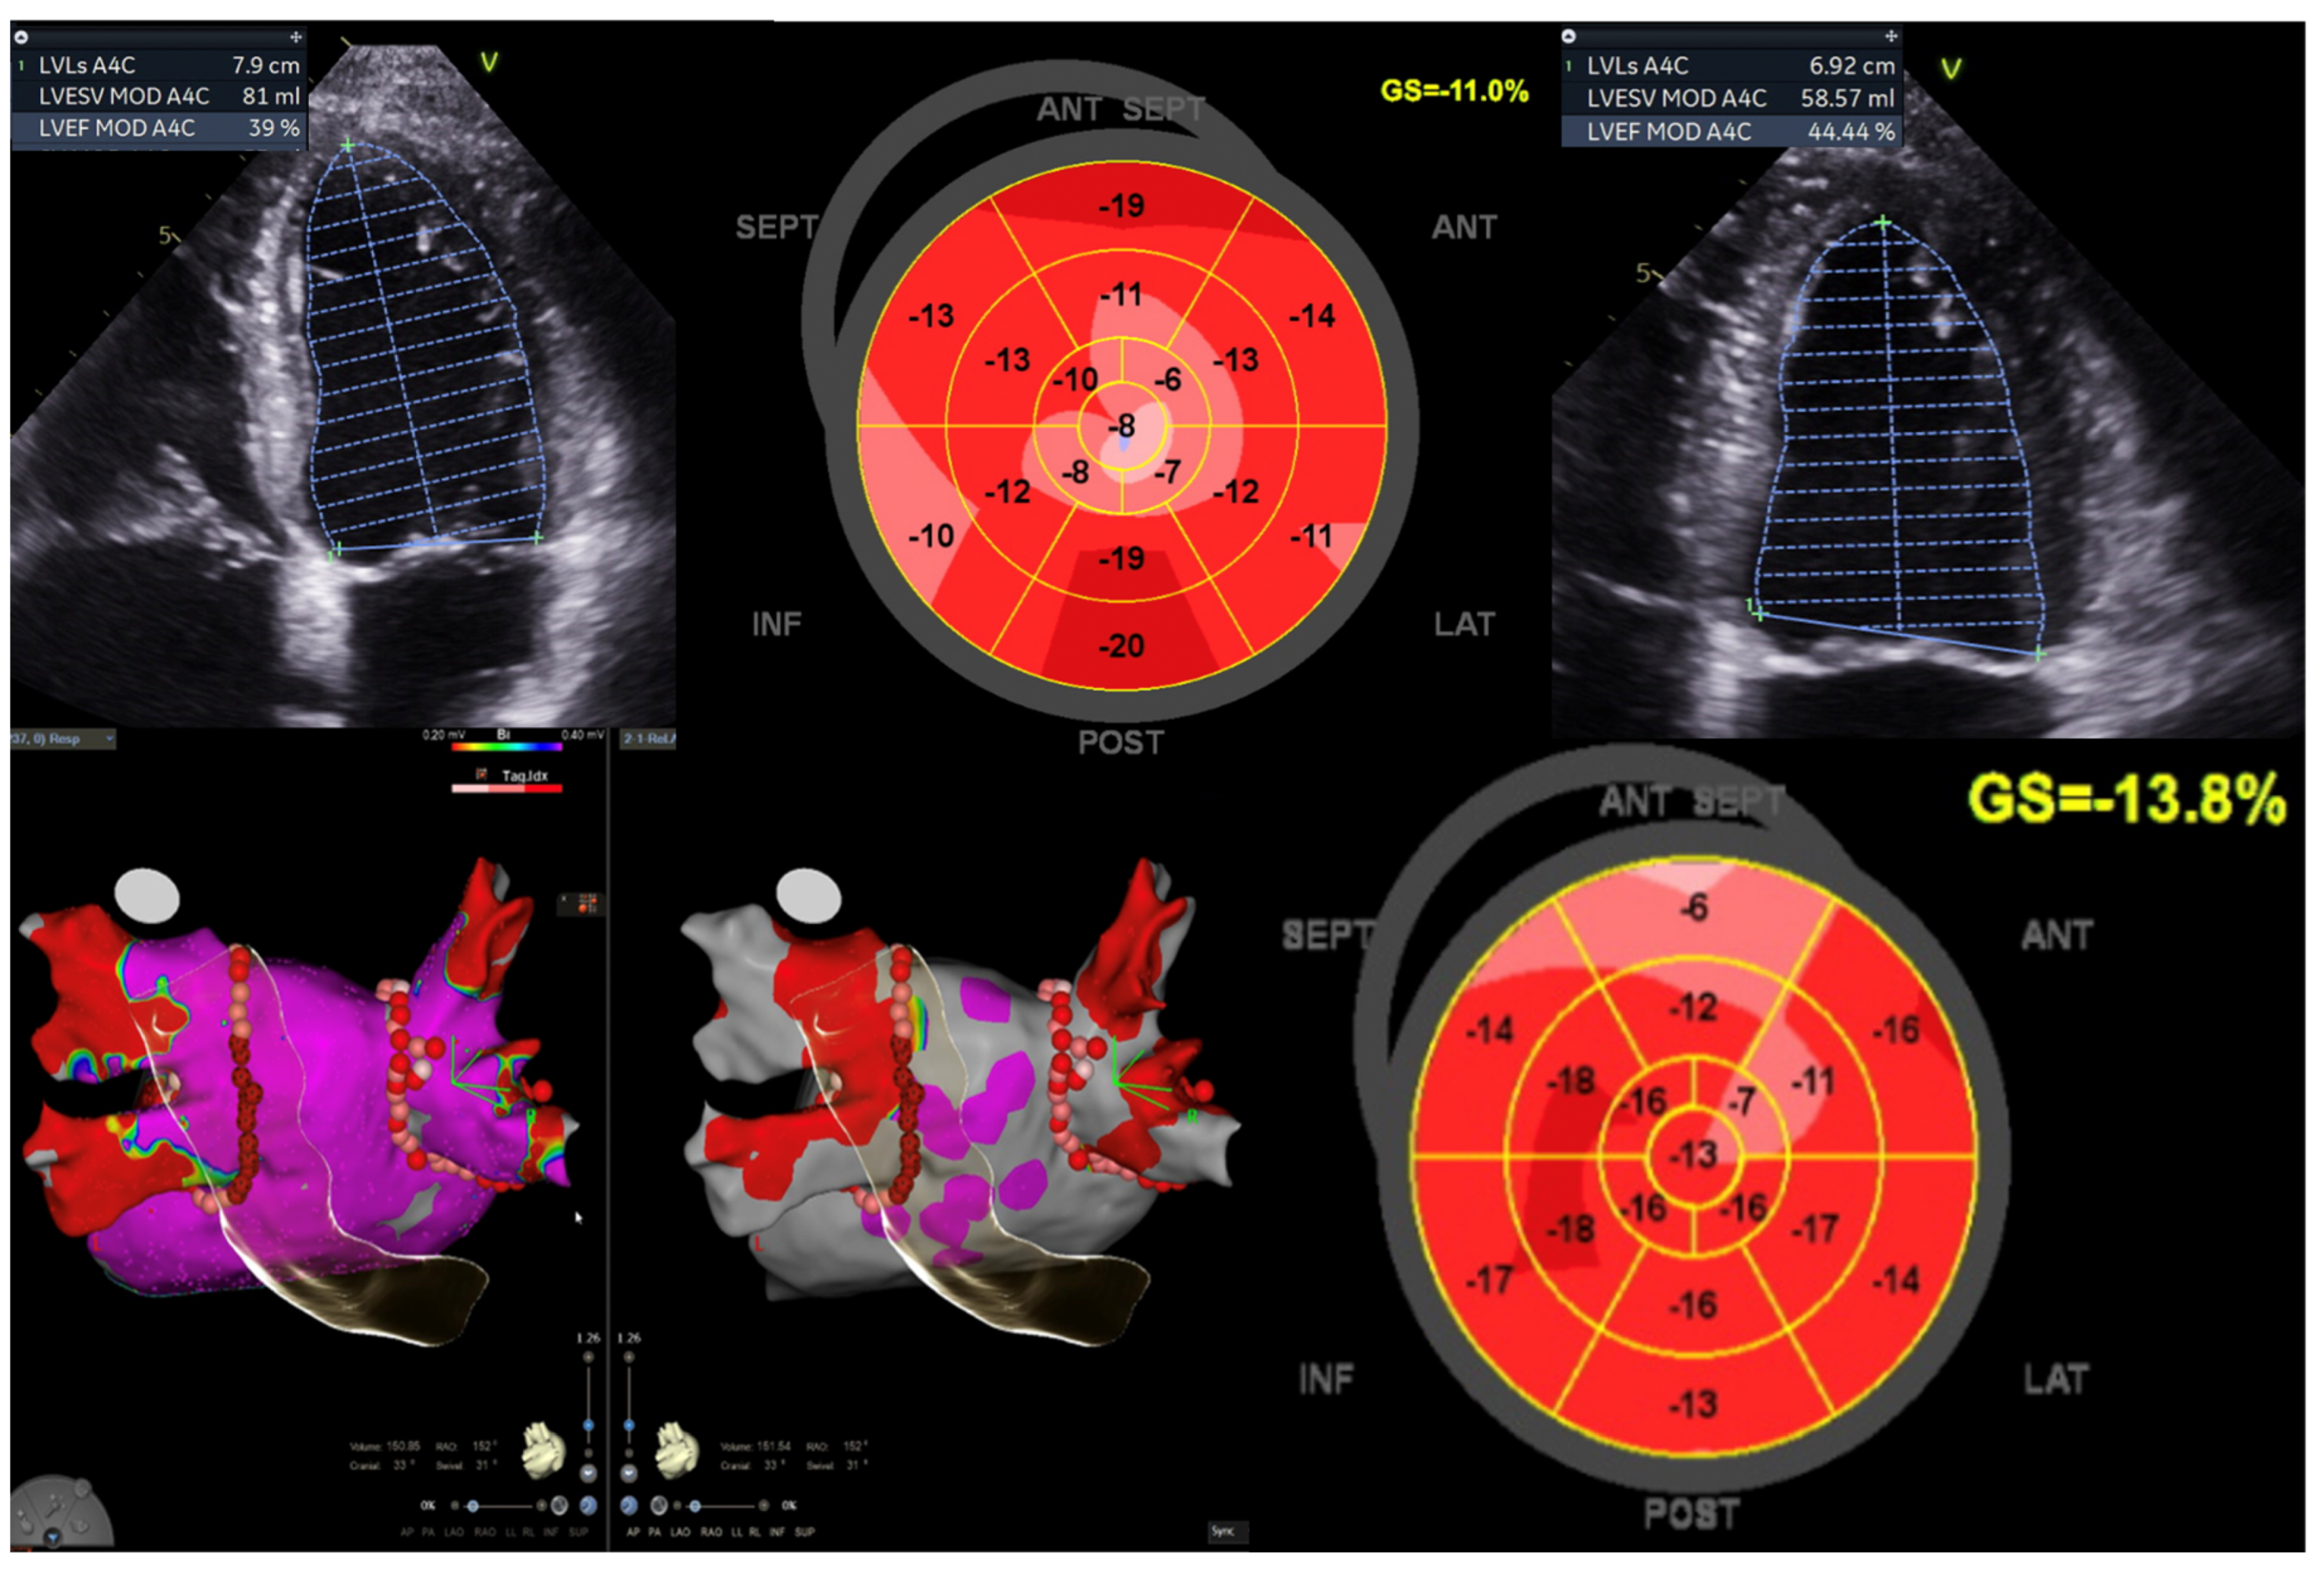

In traditional pacing protocols, initiating the electrical impulse from the right ventricle can disrupt myocardial coordination, resulting in compromised cardiac output efficiency. Conversely, contemporary methods such as left bundle branch area pacing (LBBAP) or His bundle pacing (HBP) offer a more targeted approach by directly stimulating the heart’s intrinsic conduction pathways. In cases of HFmrEF, delays in ventricular activation contribute to exacerbated HF symptoms (Figure 4). Through conduction system pacing (CSP), electrical depolarisation is delivered directly to the ventricular myocardium, minimising temporal disparities and promoting optimal electromechanical synchrony. This intervention holds some potential for enhancing cardiac performance in affected individuals.

Figure 4. Illustration of LV function improvement (EF 44.4%, GLS −13.8%) in a 52-year-old male diagnosed with Tachy-Brady syndrome with LV dysfunction (EF 39%, GLS −11%), who underwent dual chamber pacemaker-left bundle branch area pacing, followed by atrial fibrillation ablation (pulmonary vein isolation). This case underscores the significance of conduction system pacing and echocardiography when using a global longitudinal strain (GLS) assessment for evaluating improvement in LV function. Image sourced from the Canberra Heart Rhythm Centre.